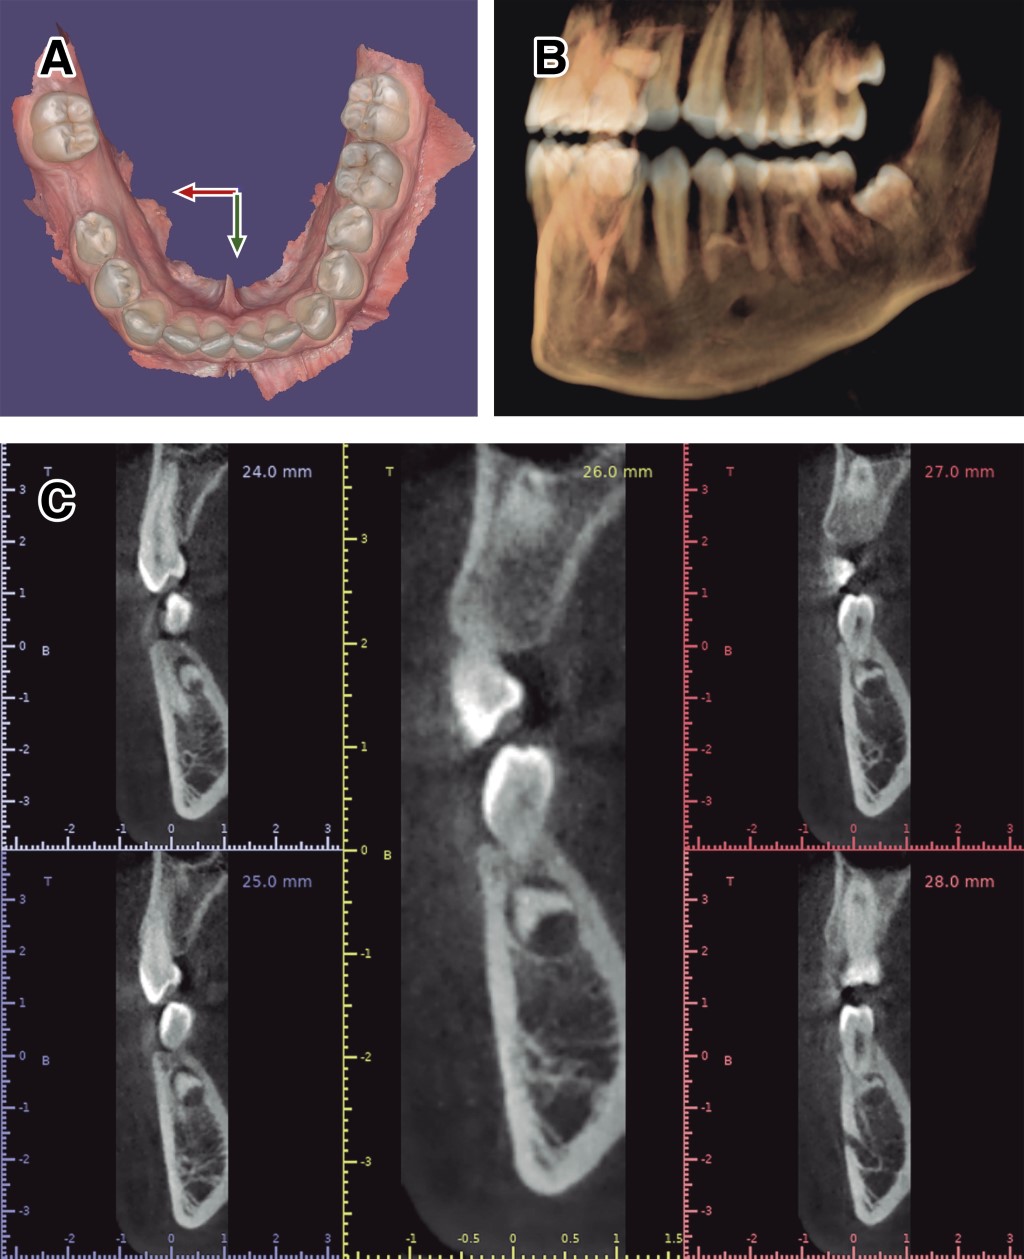

Supernumerary teeth are additional dental organs that exceed the normal number. They can present as single or multiple, unilateral or bilateral, and sometimes may be located anywhere in the dental arch, with a mandibular preference. They have the potential to cause problems with the eruption and alignment of normal dentition, which is why their treatment has often been a subject of debate. This case report describes the surgical approach of a 17-year-old male patient with dental germs present in the lower arch, located bilaterally between the premolars. The treatment plan consists of the extraction of the supernumerary tooth in quadrant 3, using various digital tools to design a surgical guide. The objective of this case is to present a surgical protocol for the extraction of a supernumerary tooth using a digital workflow.

Figure 3

Figure 4

Figure 5

Figure 6